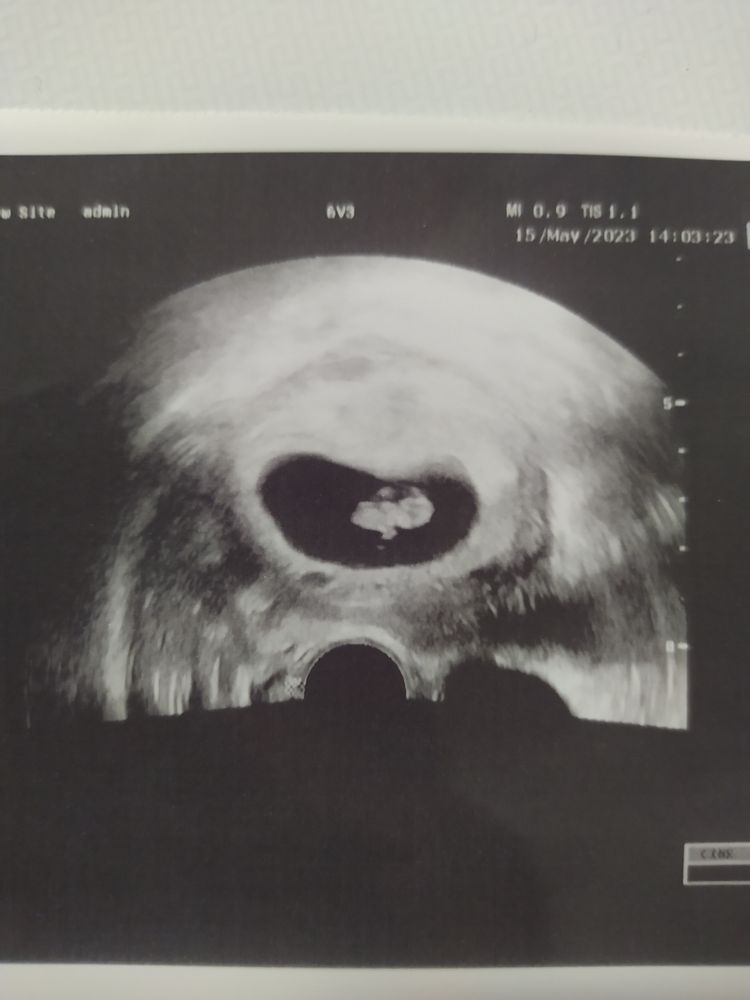

37 дпп УЗИ, 7нед.6дн.💓

СВДПЯ - 35 мм

КТР - 15,1 мм

ЖМ - 5,4 мм

ЧСС - 167 уд

На сегодня я выдыхаю. Малыш развивается точно по сроку, встретимся на скрининге🤗